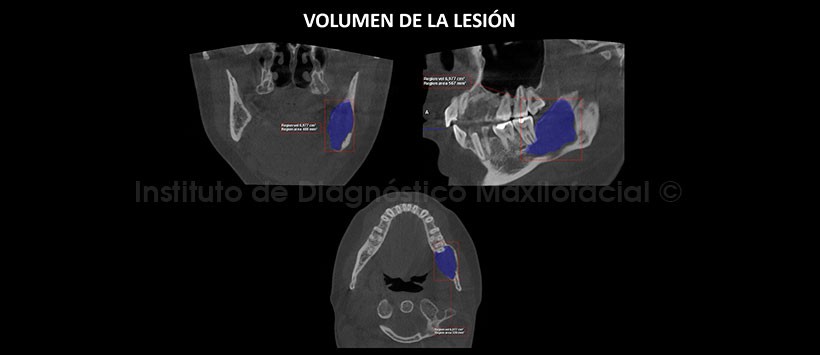

En la tomografía computarizada de haz cónico (TCHC), en los cortes multiplanares (Figura 3), cortes transaxiales (Figura 5) y cortes tangenciales (Figura 6)) se aprecia la lesión de un volumen de 6,9 cm3 (Figura 4), localizado en cuerpo y rama mandibular, que se extiende en sentido céfalo-caudal de la cima del reborde alveolar hasta el reborde basal mandibular y en sentido mesio-distal de la raíz mesial de la pieza 37 hasta el tercio inferior de la rama mandibular. La lesión ocasiona el desplazamiento y adelgazamiento de las tablas ósea vestibular, así como el desplazamiento y erosión de la tabla ósea lingual, se evidencia también el desplazamiento caudal del conducto dentario inferior